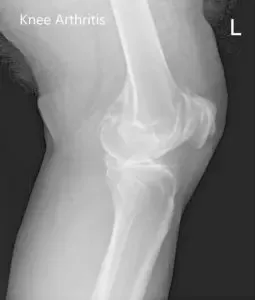

The range of motion of the left knee was full, with painful end flexion. Coronal, sagittal and rotational stress tests for instability were negative. There was no distal neurological deficit. Bilateral lower extremity pulses were 2+ and comparable. Examination of the right knee, bilateral hip, and bilateral ankles were normal. Imaging studies revealed the presence of bilateral tricompartmental osteoarthritis.

Preoperative X-ray images showing AP and lateral images of the left knee revealing tricompartmental osteoarthritis and severe medial joint space reduction.